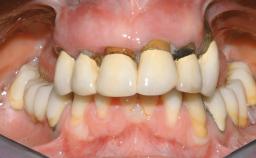

Immediate Loading of Six Implants in the Maxilla and Final Restoration with a Full-Arch CAD/CAM Zirconia FDP

A 63-year-old male patient was referred for a consultation and treatment of partial edentulism in the maxilla. The patient presented with residual anterior teeth and declined a partial removable prosthesis. He reported that the maxillary posterior teeth had been extracted due to mobility and periodontal disease two months before the consultation. The patient’s chief complaint was that his residual maxillary teeth were mobile and that he was unable to chew. The patient’s desire was a stable and comfortable fixed maxillary rehabilitation. The patient was a light smoker (fewer than 10 cigarettes/ day), and his medical history was without significant findings. He was not on any regular medication at the time of consultation. The extraoral examination revealed a normal physiognomy with a correct distribution of the facial thirds. The patient presented a low lip line, and the transition line between teeth and soft tissues was not exposed during a forced smile.

Prosthesis Type FDP

Defining Characteristics Fully edentulous upper jaw to be rehabilitated with an implant-borne fixed dental prosthesis

Provisional Implant-Supported Prosthesis Prosthodontic margin < 3 mm apical to mucosal crest Prosthodontic margin < 3 mm apical to mucosal crest